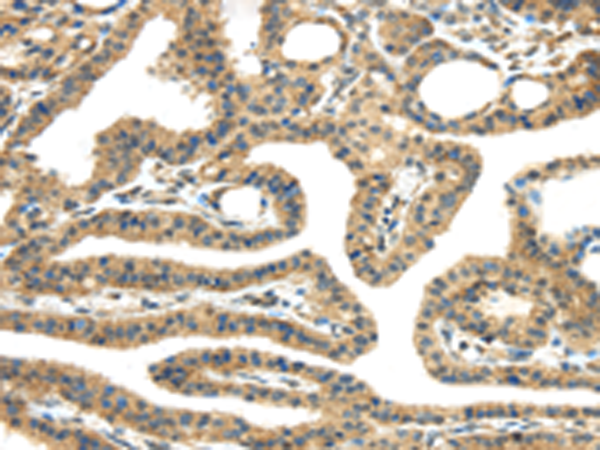

分类: 科研抗体货号: P08902别名: EG1; magicin; 1500003D12Rik应用: WB,IHC反应种属: Human, Mouse, Rat